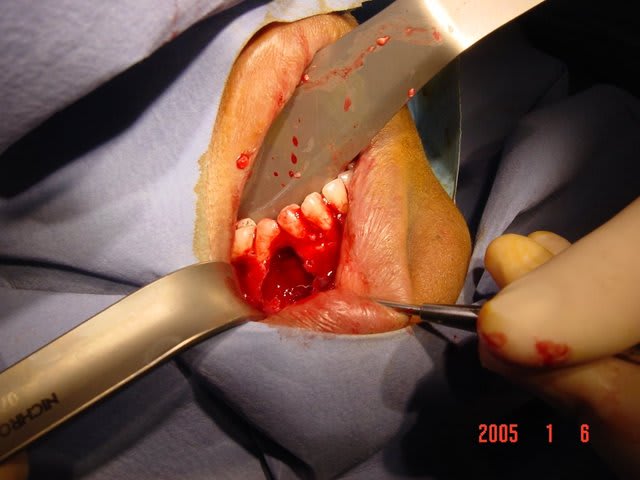

desole mais ls p^hotos sont pas top ;la panseuse est meilleur IBOD que photographe

j'ai pu donc realiser un lambeau de pleine epaisseur de 43 a 47 avec incision de decharge en mesial de 43 puis arrive au niveau du rebor basilaire j'ai disseque en epaisseur partiel.

au niveau du kyste j'ai decolle la membrane kystique en mesial distal lingual vestibulair emais pas en apical puis avec une pince hemostaqtiue tu tires doucement et il veint en un gros morceau .

ensuite tu as un acces visuel sufisant pour te permettre de nettoyer la partie apical en respectant le nerf alveolaire

une fois visualise ce n'est pas difficile de ne pas l'abimer

c'est pas plus complique qu'une resection apicale